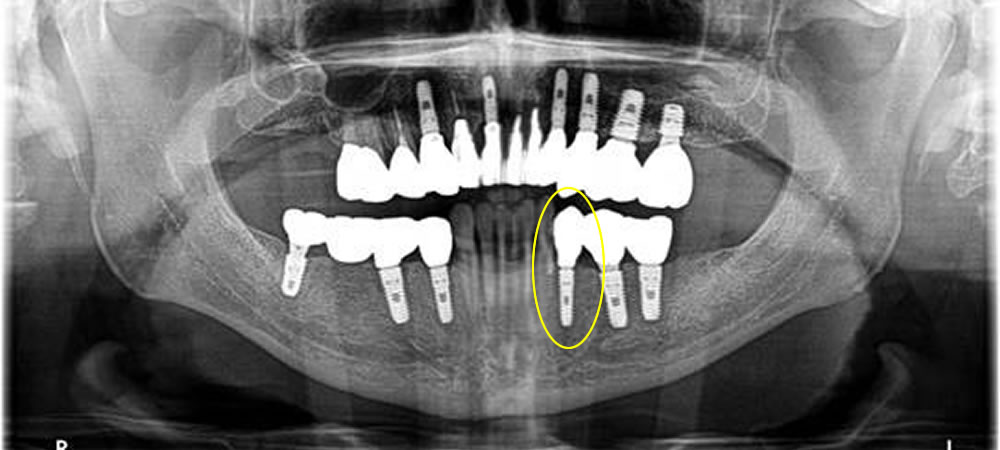

上部構造の装着・治療完了

治療後はレントゲンでも確認できるように骨もしっかりと再生し、今では固いものも噛めるようになり、患者さまに大変満足いただけました。